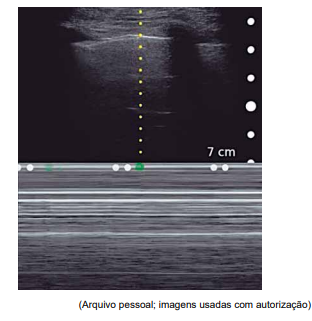

Paciente de 2 anos, internado em UTI pediátrica por

insuficiência respiratória aguda secundária à pneumonia

extensa. Intubado com cânula orotraqueal número 4 com

cuff, com bom padrão respiratório, mantendo SatO2

=

96%. Logo após atendimento da fisioterapia, apresentou

queda de saturação sustentada até 70% e assincronia

ventilatória. Exame físico com ausculta muito diminuída

em hemitórax direito, com expansibilidade também diminuída no mesmo lado. Associado a isso, houve queda de

PA para 66 x 24 (44) mmHg e piora da perfusão.

Realizou-se a ultrassonografia “point-of-care” conforme imagem a seguir, no modo M, vista em todo hemitórax direito (aspecto de “código de barras”).

Considerando esses achados, qual é a conduta adequada para a condição apresentada pelo paciente?